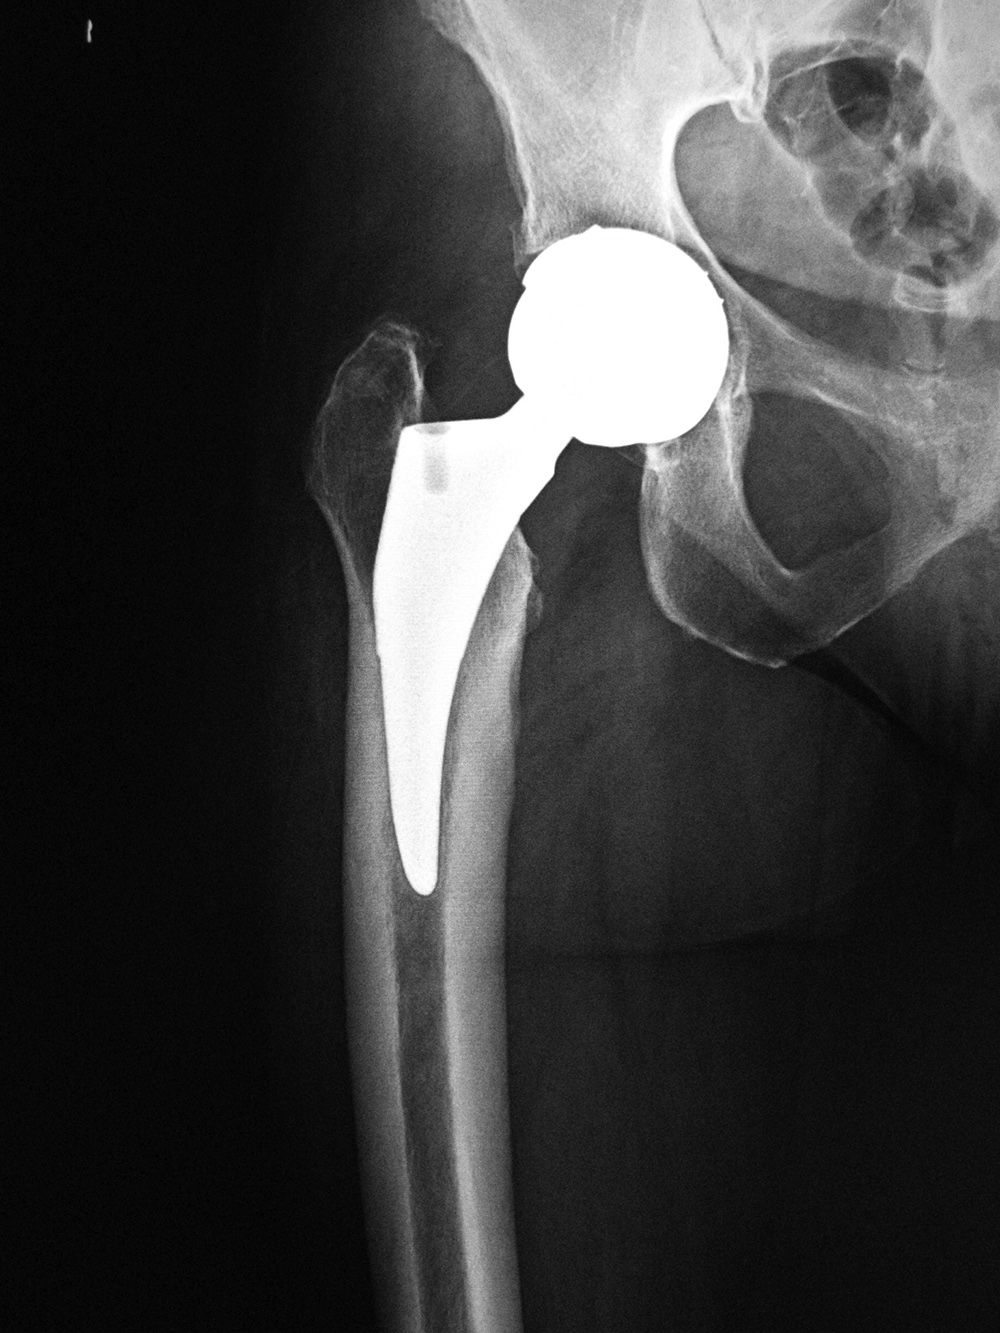

For patients younger than 65 with a normal life expectancy and adequate bone mass, cementless femoral stems are preferred (figure: bilateral total hip arthroplasty in 38 year-old man). It is possible that a femoral stem which has become well ingrown will not require revision, even if the acetabular component, and the articulating femoral head may need revision in the future. However, as in most cases with orthopedic surgery, the choice of components and the use of cemented or cementless femoral component depends on the surgeon's preference and experience. With any type of joint replacement, there is concern for its longevity and the need for ultimate revision or complete replacement. Revision surgery is usually not easy and may not have good results. Therefore, joint replacement is avoided as much as possible in younger patients and put off as long as is reasonable.

Total hip arthroplasty with porous coated stem |

67 year-old woman